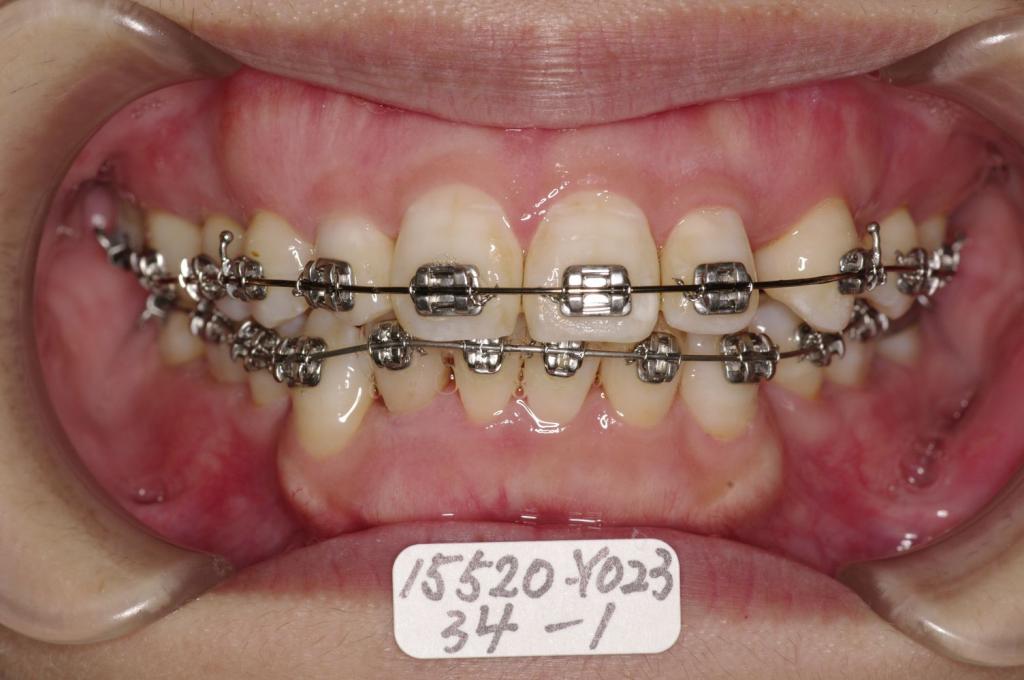

装置の種類及び治療法 診断:叢生 上下顎前突 上顎右側犬歯欠損

治療方法および装置:マルチブラケット装置

High pull J-hook headgear

抜歯:右上 /左上4

右下4 /左下4

装置写真

治療前

歯並び・咬み合わせ・八重歯・乱杭歯の矯正治療前口内写真NO.1211